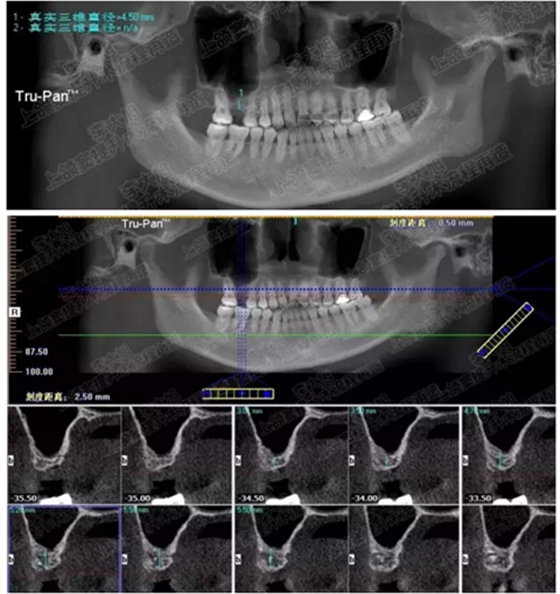

病例二

剩余骨量2mm

003.png

提升10mm

004.png